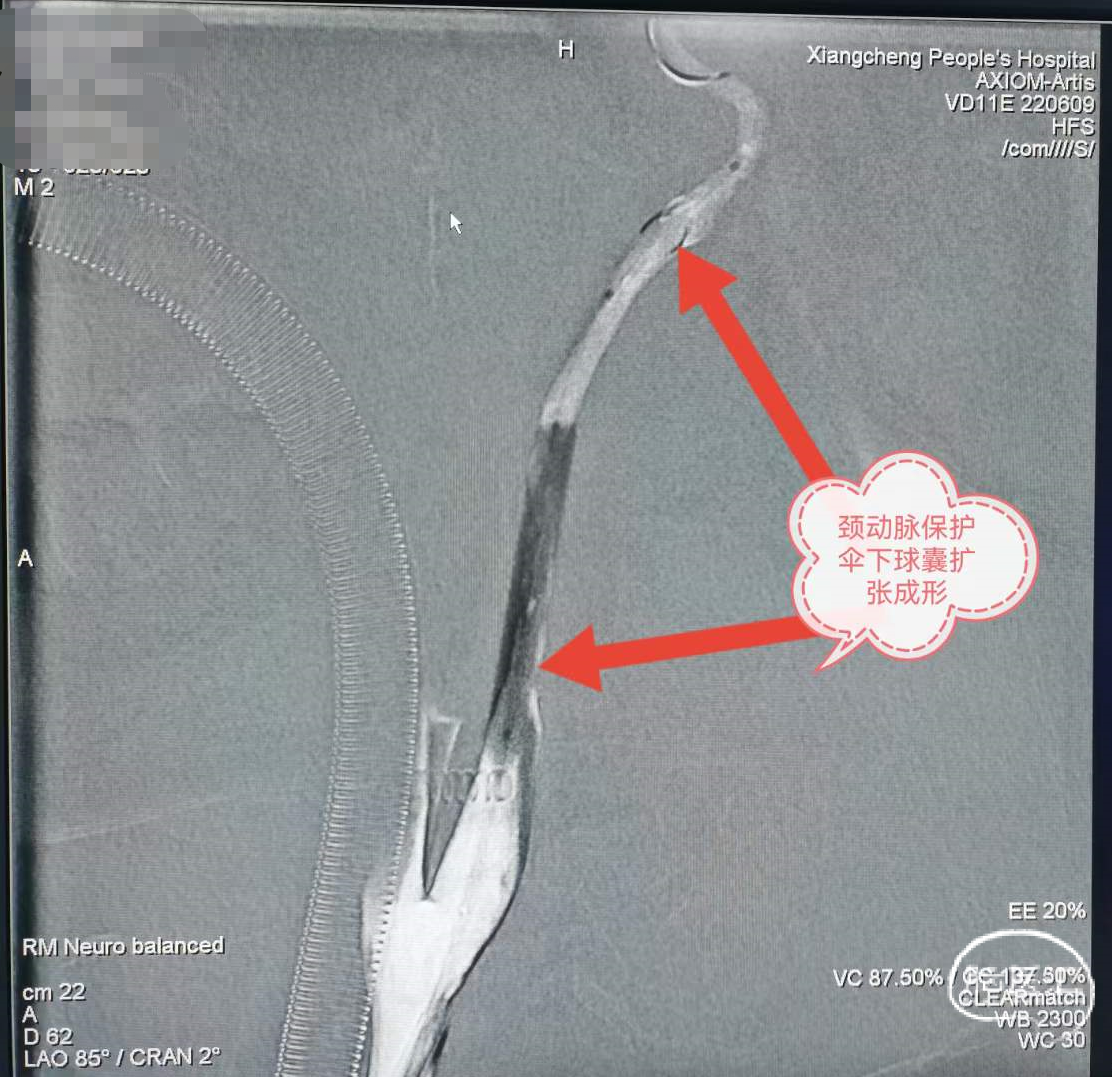

颈动脉保护伞下球囊扩张成形。

5.jpg